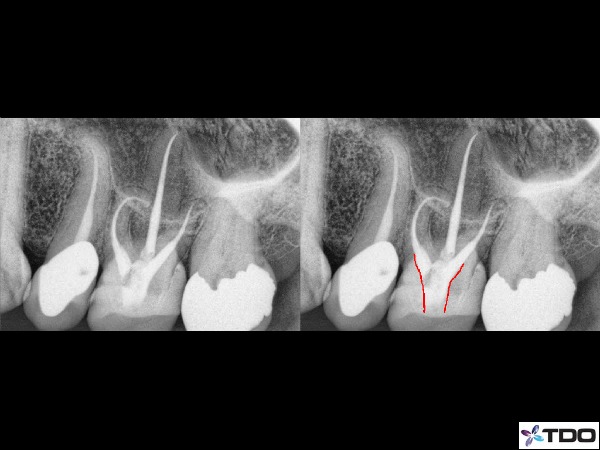

Figure 9: A conservative access form very centralized in the tooth. I need to keep this access central so not as to interfere with any lateral walls which would impact the retentive value of the crown to be place. You can see I did not at all have straight line access into the MB or MB2 canals, but the curvature was still managed carefully.

Figure 10: Another very curved canal that I did not attain perfect straight line access on the MB or MB2 canal. The access is very centralized. The illustration on the right with the red shows the location of my access through the crown.